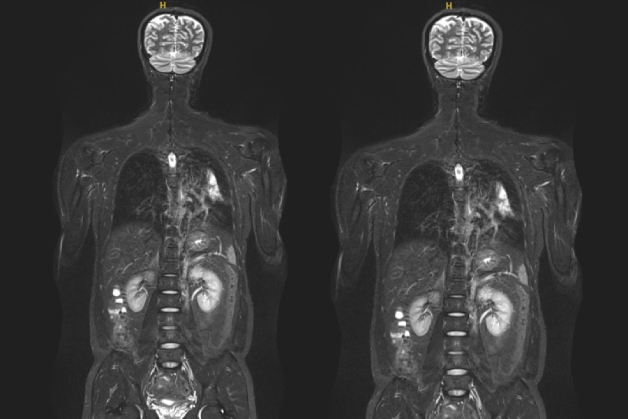

Chụp cộng hưởng từ là kỹ thuật chẩn đoán hình ảnh sử dụng từ trường và sóng radio để tái tạo hình ảnh toàn bộ cơ thể. Phương pháp chụp cộng hưởng từ mặc dù không sử dụng tia X nhưng vẫn có thể giúp bác sĩ phát hiện ra được các bất thường của cơ thể.

Hình ảnh chụp cộng hưởng từ có độ sắc nét, tương phản cao, chi tiết, rõ ràng, giải phẫu tốt. Ngoài ra, bác sĩ có thể sử dụng hình ảnh này để tái tạo 3D, tăng hiệu quả trong chẩn đoán bệnh và đánh giá được toàn bộ các cơ quan trong cơ thể, bao gồm:

Chụp cộng hưởng từ toàn thân giúp phát hiện các dấu hiệu bất thường bên trong cơ thể với chất lượng hình ảnh rõ nét nhất